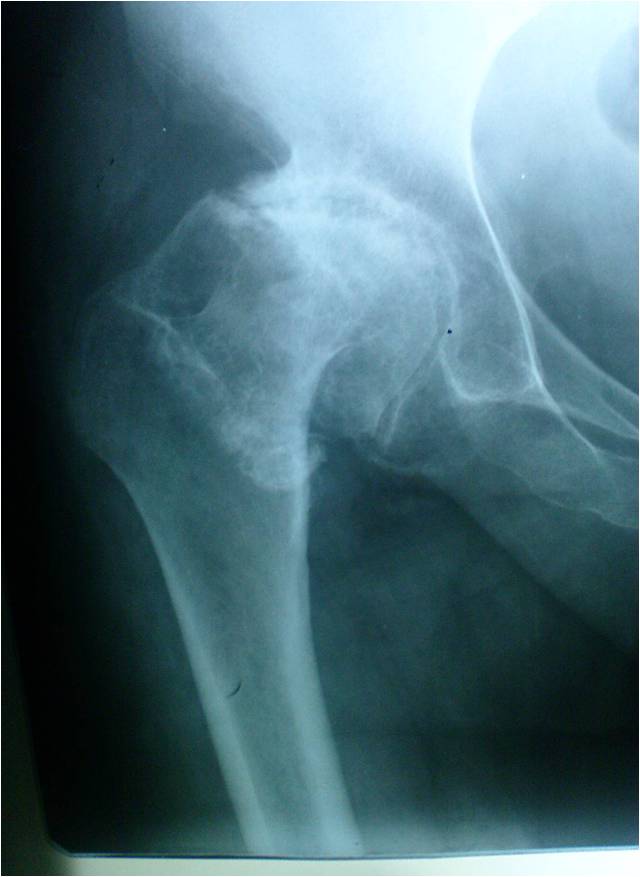

Austin Moore & Thompson in a 95 year old Egyptian lady